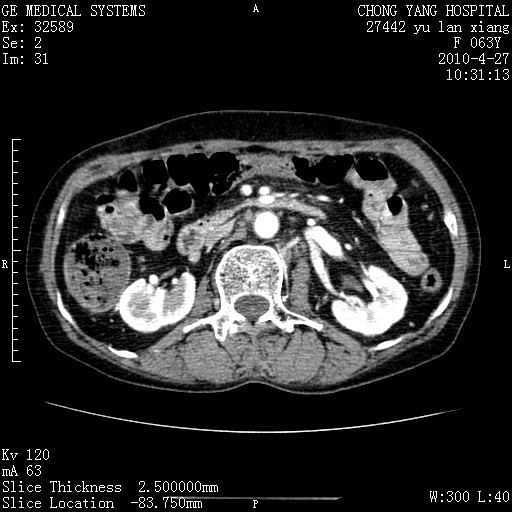

标题: CT26066:F63Y 上腹正中压痛半月,CA199:7400u/ml,MR示胰腺炎伴 [打印本页]

胰腺癌侵犯腹腔动脉干-分支、胃壁、左侧膈肌伴胰周及腹膜后淋巴结转移、胆囊切除术后。

胰腺癌侵犯腹腔动脉干-分支、胃壁、左侧膈肌伴胰周及腹膜后淋巴结转移、胆囊未显影。